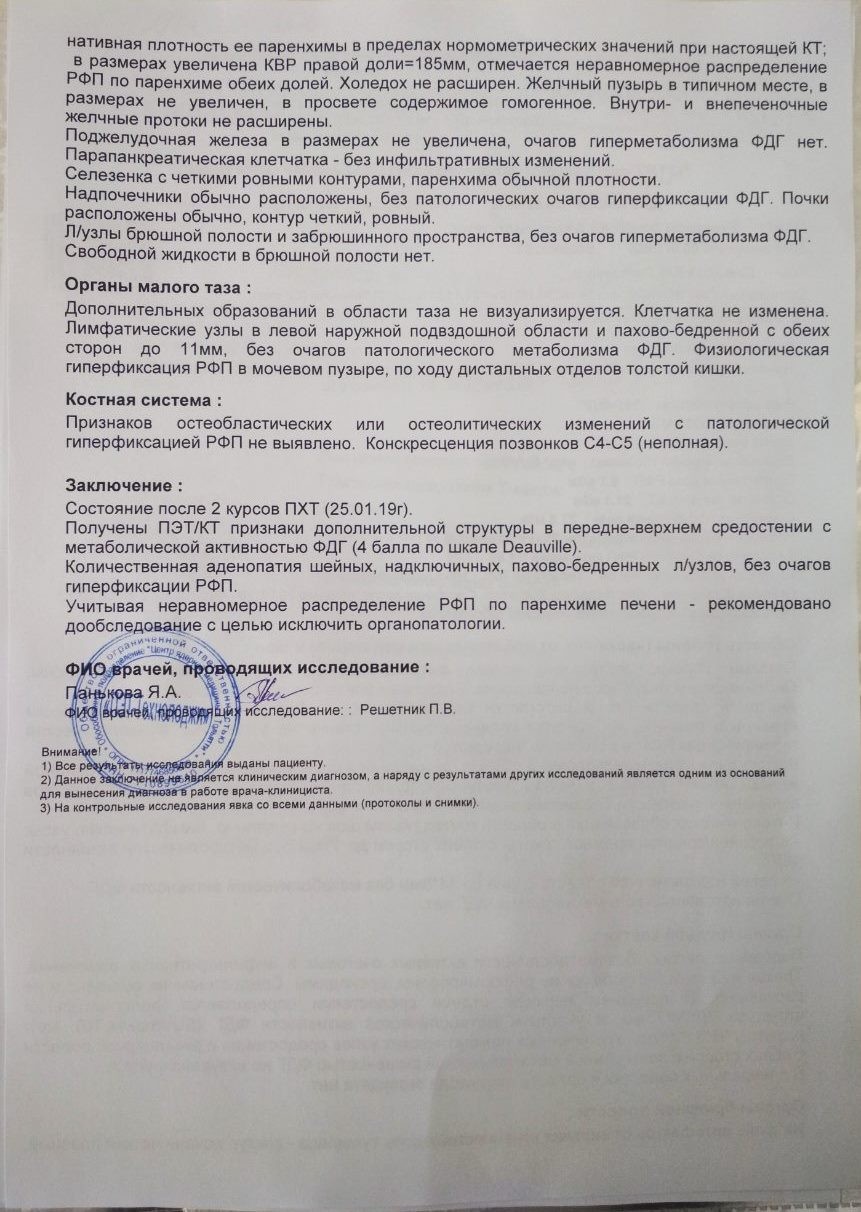

Диагностика лимфомы Ходжкина с помощью ПЭТ и КТ

Раздел: Светлые идеи